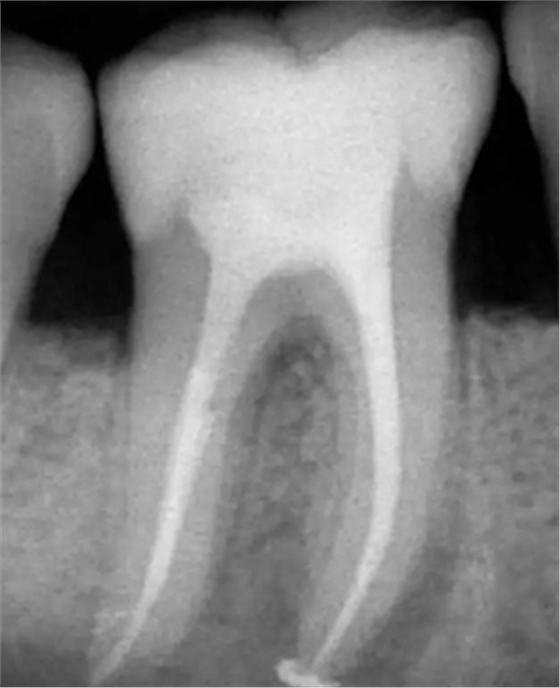

術(shù)前X片

高嵌體粘固后X片